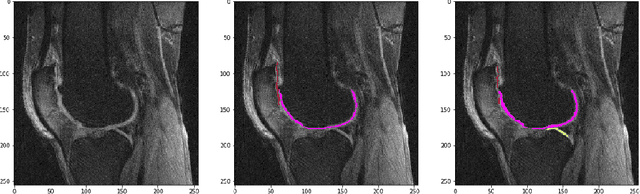

Abstract:The integrity of articular cartilage is a crucial aspect in the early diagnosis of osteoarthritis (OA). Many novel MRI techniques have the potential to assess compositional changes of the cartilage extracellular matrix. Among these techniques, diffusion tensor imaging (DTI) of cartilage provides a simultaneous assessment of the two principal components of the solid matrix: collagen structure and proteoglycan concentration. DTI, as for any other compositional MRI technique, require a human expert to perform segmentation manually. The manual segmentation is error-prone and time-consuming ($\sim$ few hours per subject). We use an ensemble of modified U-Nets to automate this segmentation task. We benchmark our model against a human expert test-retest segmentation and conclude that our model is superior for Patellar and Tibial cartilage using dice score as the comparison metric. In the end, we do a perturbation analysis to understand the sensitivity of our model to the different components of our input. We also provide confidence maps for the predictions so that radiologists can tweak the model predictions as required. The model has been deployed in practice. In conclusion, cartilage segmentation on DW-MRI images with modified U-Nets achieves accuracy that outperforms the human segmenter. Code is available at https://github.com/aakashrkaku/knee-cartilage-segmentation